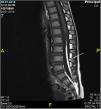

In the initial evaluation a lumbar ultrasound (US) was made showing no structural anomalies. A few months later, the lesion decreased in size but we decided to request a magnetic resonance image (MRI) to complete the study. The MRI demonstrated a 4mm lipoma in association with the conus medullaris and the filum terminale with tethered cord (fig. 2). We extend the study to other urologic anomalies resulting negative. The girl was derived to pediatric neurosurgery for evaluation where she was operated performing a medullary repair of the tethered cord (fig. 3) with good response and normal psychomotor development.

We requested a US that revealed a persistent dermal sinus and a MRI that showed a filum terminale lipoma (fig. 5). With these findings we also performed a urological evaluation that resulted normal. The patient was sent to the pediatric neurosurgery unit for evaluation where they decided to maintain follow up due to the normal neurological clinic.

Case 3A 1-month-old boy who came to our department for presenting a sacral hemangioma, with no other associated clinic. Son of healthy parents, had a uncomplicated pregnancy and delivery. The physical examination showed an ulcerated hemangioma of 3cm with presence of sacral fossa and asymmetry of the intergluteal fold. Treatment with propranolol was started with a very good response. A study was performed with ultrasound that result normal and later MRI that demonstrates the presence of a lipoma of the filum terminale without tethered cord (fig. 6). He was derived to pediatric neurosurgery for evaluation, who decide on conservative management and follow-up.

Another retrospective study have classified the different types of spinal anomalies associated with cutaneous lumbosacral hemangiomas. They included children with hemangiomas >2.5cm associated to spinal dysraphism in the MRI. They analyzed 20 cases and found tethered cord in 60%, spinal lipoma in 50%, intraspinal hemangiomas in 45% and sinus tract was found in 40% of children. With this information they recommended a imaging protocol of MRI sequences of the thoracolumbar junction and lumbosacral spine in the background of cutaneous lumbosacral hemangioma.26